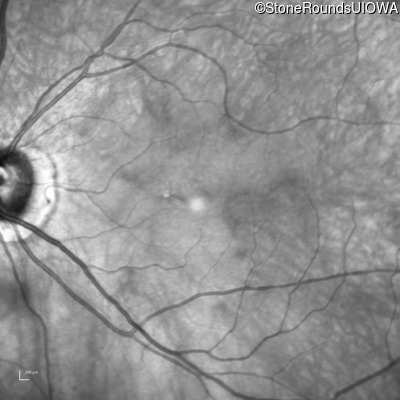

The clinical features favoring the diagnosis of RP1L1-associated occult macular dystrophy include: reduced acuity with a near-normal ophthalmoscopic appearance, a history of normal acuity in childhood; and, a "moth-eaten" appearance of the macular ellipsoid zone on OCT.

OD OS